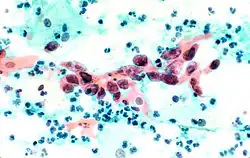

The stain should result in cells that are fairly transparent so even thicker specimens with overlapping cells can be interpreted.[2] Cell nuclei should be crisp, blue to black in color[12][13] and the chromatin patterns of the nucleus should be well defined. Cell cytoplasm stains blue-green and keratin stains orange in color.[13][5]

Eosin Y stains the superficial epithelial squamous cells, nucleoli, cilia, and red blood cells.[2] Light Green SF yellowish confers a blue staining for the cytoplasm of active cells such as columnar cells, parabasal squamous cells, and intermediate squamous cells.[14] Superficial cells are orange to pink, and intermediate and parabasal cells are turquoise green to blue.[12]

Squamous cell carcinoma in the cervix.